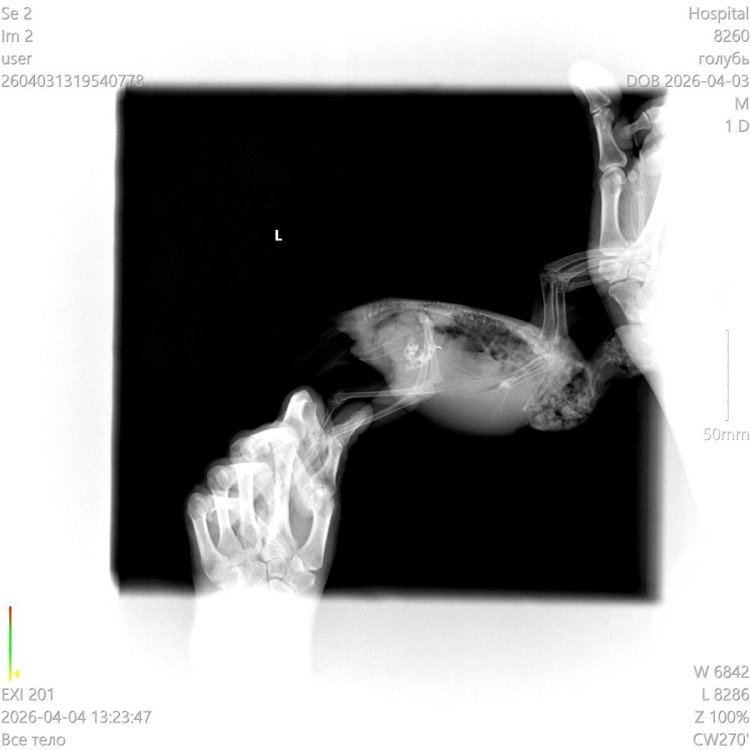

Зося ответила. Я ,, подсуетилась,, . ,, нужен снимок в латеральной проекции. Пока не видно скорлупы , виден крупный объект округлой формы ( полноценное яйцо имеет иную форму).,, вот , что ттве Зося Только не пойму, с какого бока ее фотографировать 🤔 с которого виден желудок или с другого 🤔 Вот этим Вы бы мне помогли Пробовала, пишет ошибку

После обеда будет боковая проекция. Записалась на 13.30 . НаТуся все равно горбатится. Обезбол Ибупрофен не давала сегодня т к. с утра перья чистила, потягивала лапками крылья, по подоконнику ходит. Сегодня активная. Но не буду рано радоваться... Ест самостоятельно, вот насчет воды, так и не видела, чтобы пила, но уровень меняется в плашке Ни вацап, ни телеграм. Макс работает

@Patata да, мне тоже ответила. Тогда ждем второй снимок и что скажет Зося